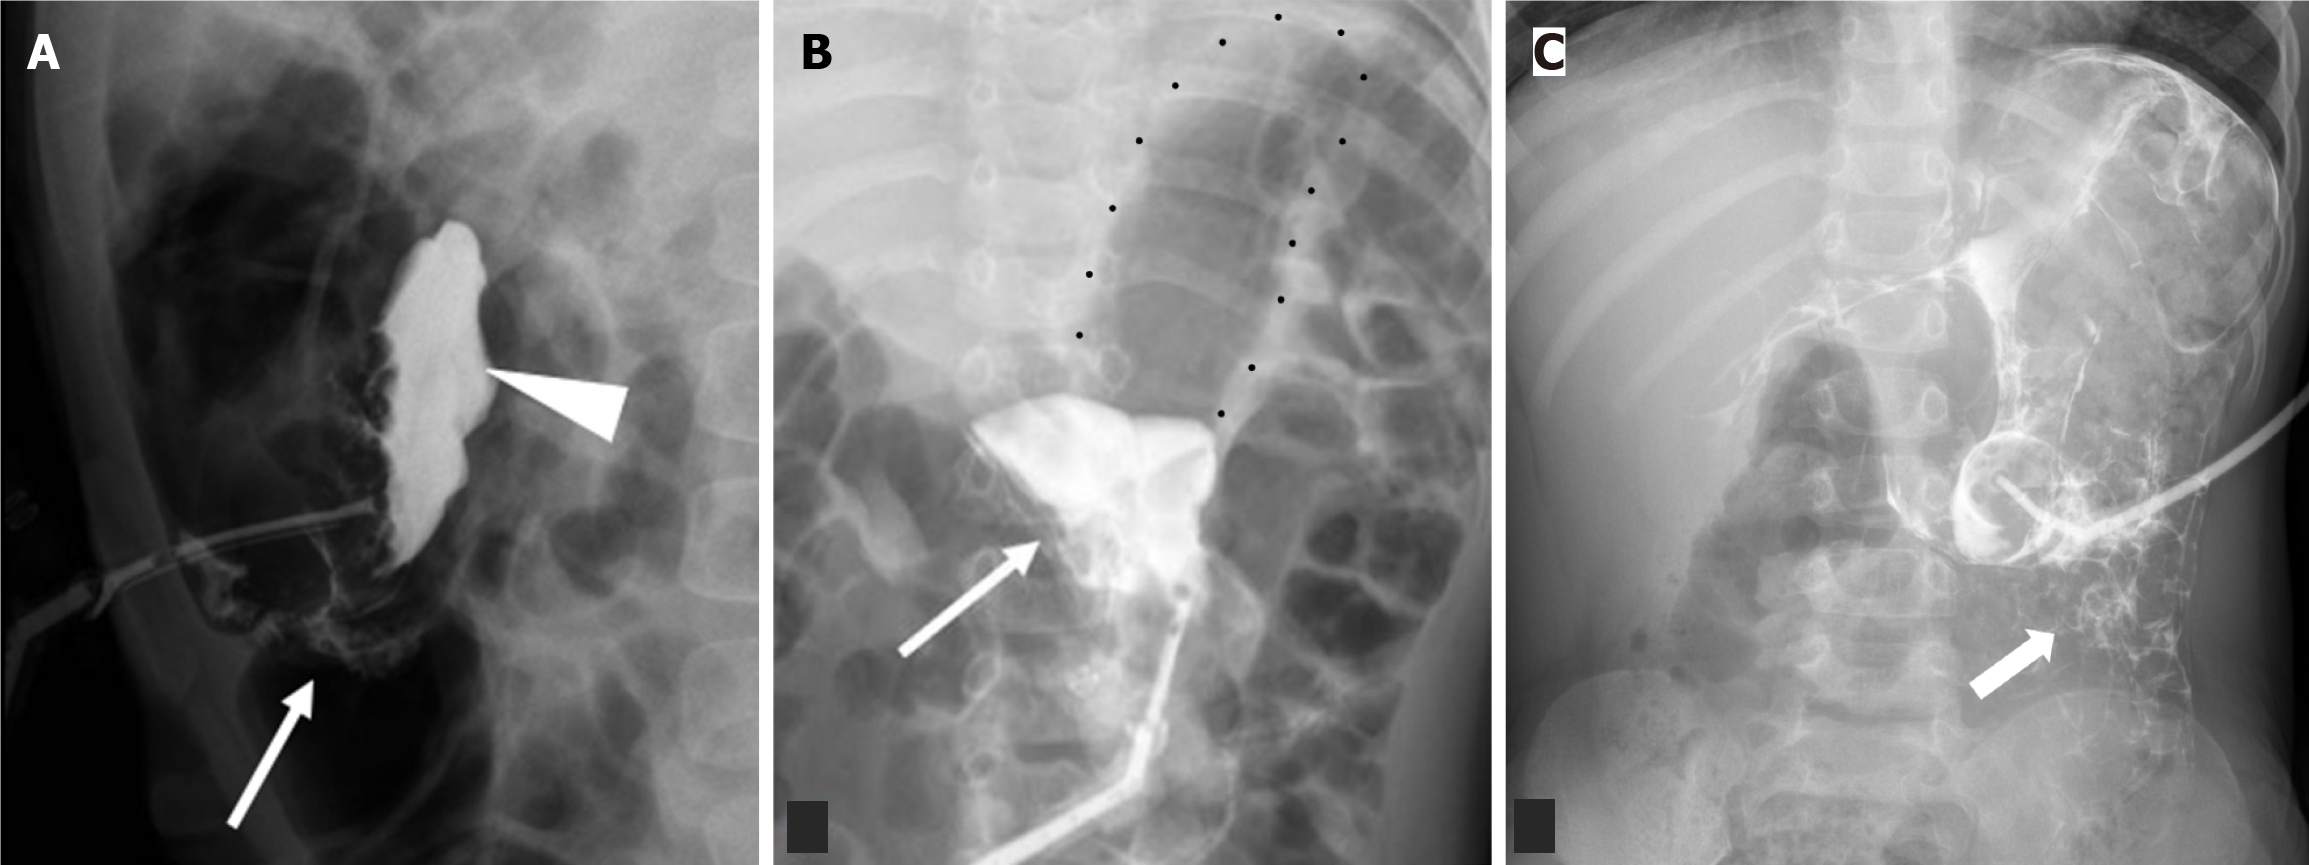

Figure 3 Free peritoneal spillage of contrast.

A: Lateral radiograph of a 1-year-old with recently exchanged tube. Injected contrast pools in the intraperitoneal cavity (arrowhead) which does not follow the stomach contour with outlining of bowel loops (arrow); B: Frontal radiograph irregular or angular margins of the injected contrast (arrow) (multiple black dots outlining the air filled stomach); C: Frontal radiograph of another 4-year-old boy demonstrates similar extrinsic outlining of bowel loops.